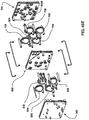

- Fig. 1 is a schematic representation of a hemodialysis system.

- the system 5 includes two flow paths, a blood flow path 10 and a dialysate flow path 20.

- Blood is drawn from a patient.

- a blood flow pump 13 causes the blood to flow around blood flow path 10, drawing the blood from the patient, causing the blood to pass through the dialyzer 14, and returning the blood to the patient.

- the blood may pass through other components, such as a filter and/or an air trap 19, before returning to the patient.

- anticoagulant may be supplied from an anticoagulant supply 11 via an anticoagulant valve 12.

- a dialysate pump 15 draws dialysate from a dialysate supply 16 and causes the dialysate to pass through the dialyzer 14, after which the dialysate can pass through a waste valve 18 and/or return to the dialysate feed via dialysate pump 15.

- a dialysate valve 17 controls the flow of dialysate from the dialysate supply 16.

- the dialyzer is a type of filter having a semi-permeable membrane, and is constructed such that the blood from the blood flow circuit flows through tiny tubes and the dialysate solution circulates around the outside of the tubes. Therapy is achieved by the passing of waste molecules (e.g., urea, creatinine, etc.) and water from the blood through the walls of the tubes and into the dialysate solution. At the end of treatment, the dialysate solution is discarded.